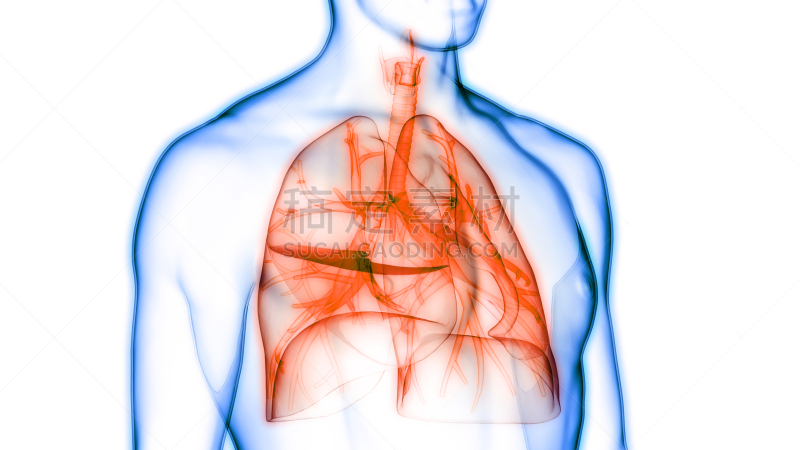

人体呼吸系统肺解剖学详情

JPG